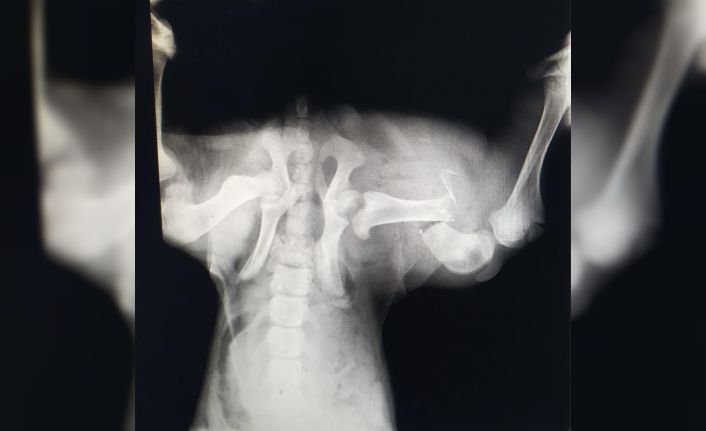

Edinilen bilgiye göre, İzmit’te trafik kazası geçiren sokak köpeği, bir vatandaş tarafından özel veteriner kliniğine götürüldü. Burada köpeğin genel durumunun çok kötü olduğu ve uyutulması gerektiği belirtildi. Ancak vatandaşın vicdanı el vermeyerek, sokak köpeğini Patilik Sokak Hayvanları Kasabasına getirdi. Patilik’te tetkiklerde köpeğin arka bacağında ciddi kırık bulunduğu belirlendi. Bursa Uludağ Üniversitesi Veteriner Fakültesi Cerrahi Anabilim Dalı Bölümünden Prof. Dr. Hakan Salcı’nın gözetiminde uzman hekimler tarafından kan tahlili yapılan ve röntgeni çekilen sokak köpeğinin ayağına plaka takıldı. Sokak köpeğine cerrahi operasyondan sonra ilaç tedavisi de uygulandı.

Patilik’ten yapılan açıklamada, "Patilik Mutlu Sokak Hayvanları Kasabasına getirilen ve arka sağ bacağında kırık bulunan sokak köpeği başarılı bir operasyon geçirerek sağlına kavuştu. Patiliğ’e ilk getirildiğinde hayati verileri çok düşüktü, 6 aylık kangal sokak köpeği Patilik’te tekrar hayat buldu" denildi.